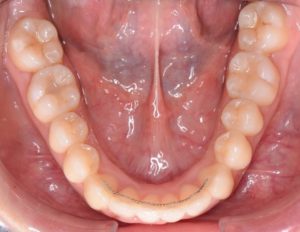

①フィックス

歯の裏側に付けるワイヤータイプの装置です。

当医院では、裏側の装置で治療した場合は保定装置(リテーナー)も目立たないように、このワイヤーを上下の前歯の裏側に付けます。

表側の装置で治療した場合は、後戻りしやすい前歯のみフィックスを付けます。